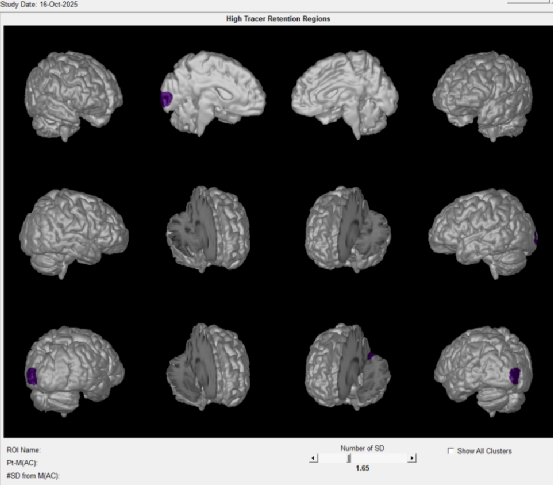

患者aβ-淀粉样蛋白 PET/CT图像:(显像剂:18F-AV45)

诊断意见:大脑双侧枕叶皮质初级视觉皮层aβ淀粉样蛋白(轻度)沉积阳性,以左侧为主。